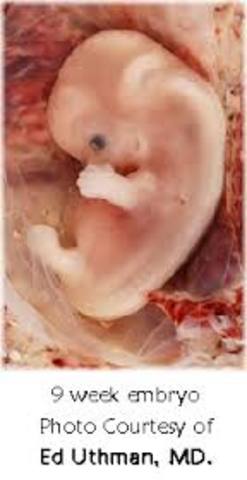

• Week 9

Week 9

Embryo starts growing bones and cartiliage. Now has a fully developed and working heart. Eyelids are begining to show however will not open for many weeks later.